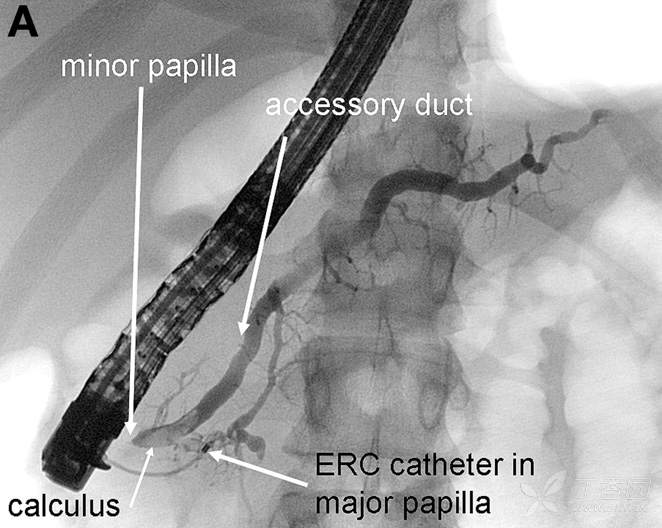

患者经禁食、静脉补液等治疗后症状缓解。因为3次反复胰腺炎发作,故行ERCP进一步明确病因,造影所见如下图:

请问:诊断是什么?

A 胰腺囊性纤维化 B 遗传性慢性胰腺炎 C 胆胰管汇流异常 D 胰腺分裂症